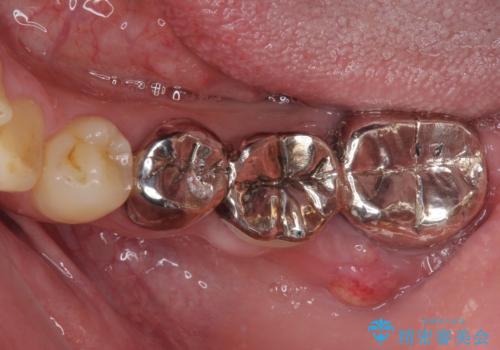

診察を行ったところ、奥の土台になっている歯は神経組織が失活しており、根尖部に病変があり、そこが原因で痛みを生じている状態でした。

根管治療を行うためにブリッジを除去したところ、むし歯が歯肉の奥深くにあまで及んでいたため、歯周外科処置によりむし歯が歯肉縁より浅い位置へと改善することとしました。